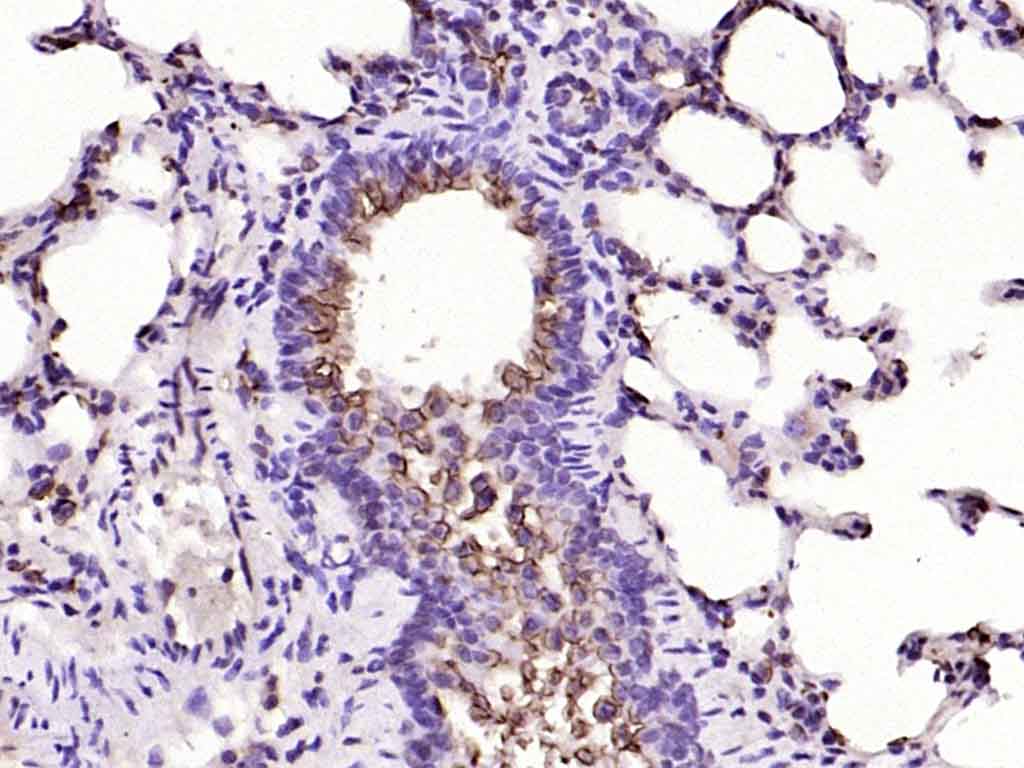

| 英文名称 | MUC1 Rabbit pAb |

| 中文名称 | 粘蛋白-1抗体 |

| 背景资料 | MUC1 is a large cell surface mucin glycoprotein expressed by most glandular and ductal epithelial cells and some hematopoietic cell lineages. It is expressed on most secretory epithelium, including mammary gland and some hematopoietic cells. It is expressed abundantly in lactating mammary glands and overexpressed abundantly in >90% breast carcinomas and metastases. Transgenic MUC1 has been shown to associate with all four cebB receptors and localize with erbB1 (EGFR) in lactating glands. The MUC1 gene contains seven exons and produces several different alternatively spliced variants. The major expressed form of MUC1 uses all seven exons and is a type 1 transmembrane protein with a large extracellular tandem repeat domain. The tandem repeat domain is highly O glycosylated and alterations in glycosylation have been shown in epithelial cancer cells. |

文献和实验[IF={{ 8.46 }}] {Taki, K., et al. "GNASR201H and KrasG12D cooperate to promote murine pancreatic tumorigenesis recapitulating human intraductal papillary mucinous neoplasm." Oncogene 35.18 (2016): 2407-2412.} {IHC} {="Mouse"}

[IF={{ 7.1 }}] {Kiyoshi Saeki. et al. Acvr1b Loss Increases Formation of Pancreatic Precancerous Lesions From Acinar and Ductal Cells of Origin. CELL MOL GASTROENTER. 2024 Jan;18:101387} {IHC} {Mouse}